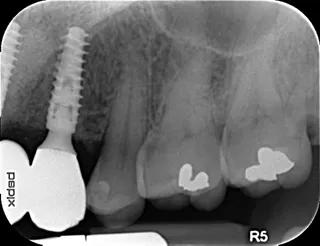

17a-b-c-d. Retro-alveolar X-rays at the end of treatment. Note bone behavior around the 4 implant collars. Soft tissue height above each collar was 3 to 4 mm.